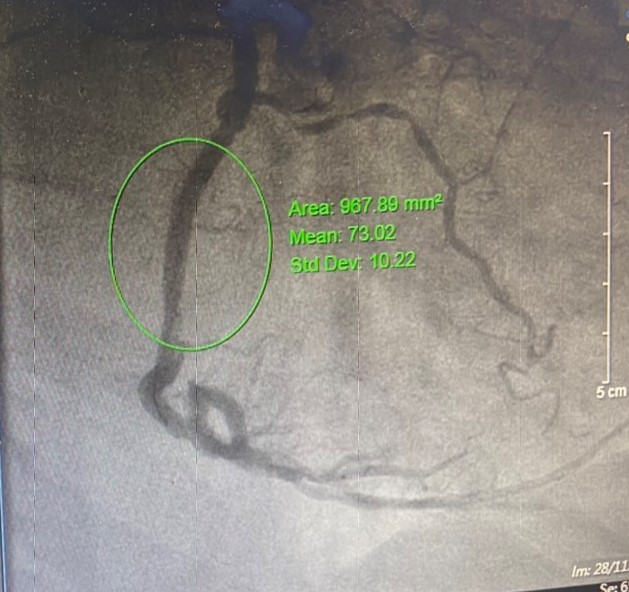

Kết quả chụp mạch vành phát hiện, tổn thương nặng 3 thân mạch vành, tắc mãn tính động mạch liên thất trước LAĐ, tắc hoàn toàn do xơ vữa và huyết khối động mạch RCA, hẹp 80-90% động mạch mũ. Dựa vào điện tim, các đánh giá và hình ảnh trên phim chụp cho thấy, thủ phạm gây tình trạng sốc tim, nhồi máu cơ tim cấp lần này là do tắc hoàn toàn động mạch vành phải RCA. Với sự phối hợp nhịp nhàng, chặt chẽ giữa các Khoa: Gây mê hồi sức, Tim mạch – Đột quỵ, kíp bác sĩ đã nhanh chóng tiến hành can thiệp đặt stent động mạch RCA, sau đó tái thông hoàn toàn, tuần hoàn dòng chảy tốt. Sau can thiệp, nhịp tim, huyết động bệnh nhân đã trở về bình thường, huyết áp tốt, hết đau ngực, được theo dõi và điều trị tại Khoa Tim mạch – Đột quỵ.